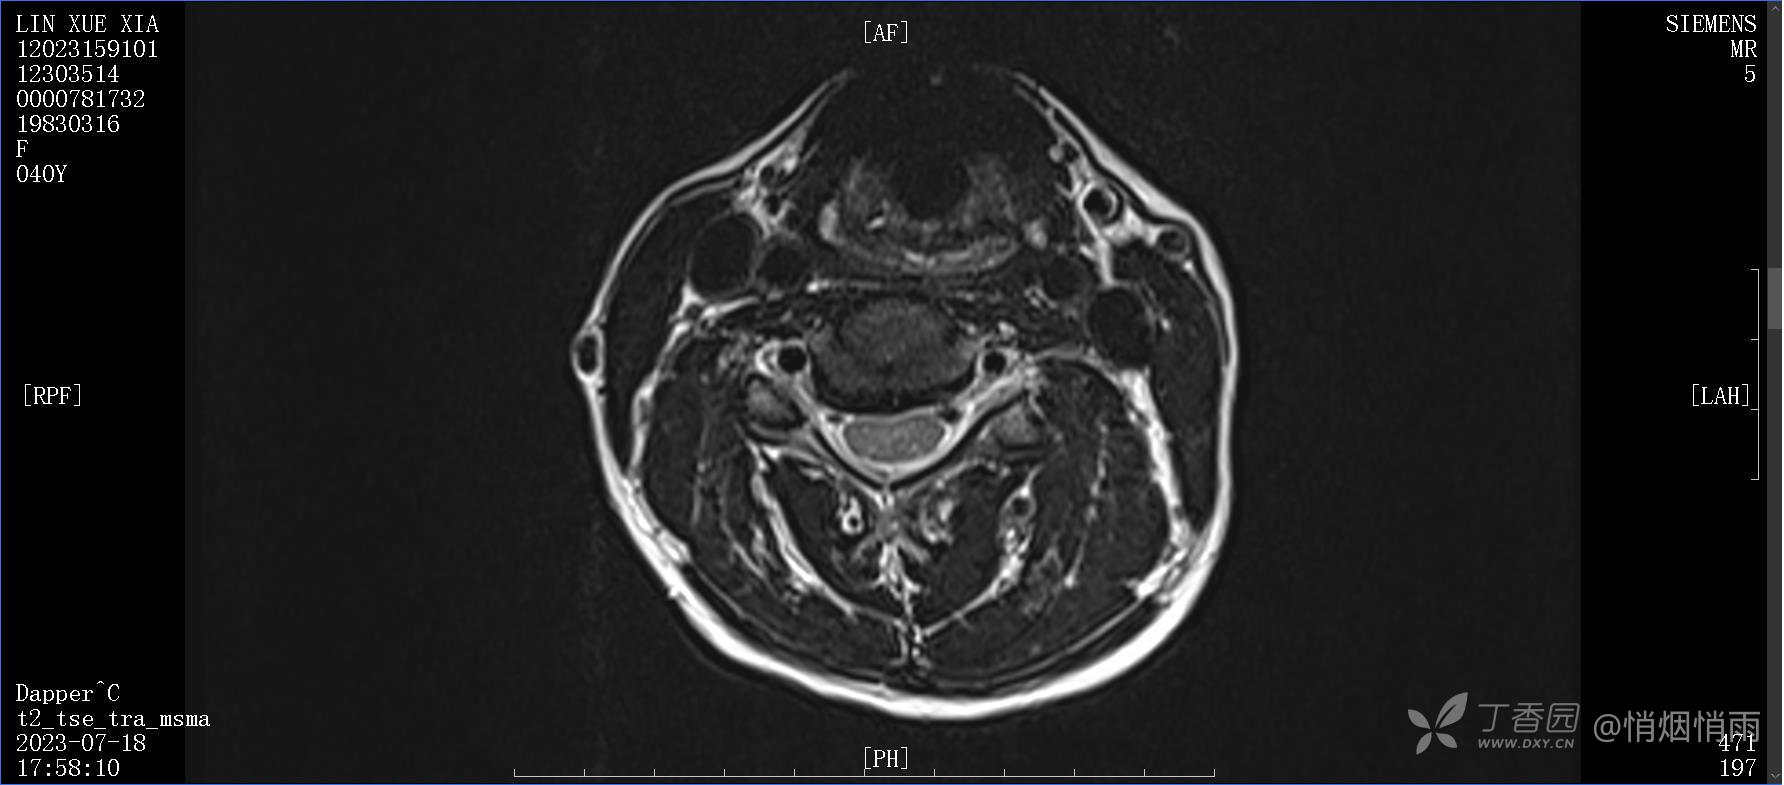

辅助检查:

目前的诊断,暂时依据辅助检查诊为肩袖损伤,但是患者疼痛的性质和特点,却不是单纯的肩袖损伤所致。考虑过胸廓出口综合征,但是该疾病会出现肩胛区的疼痛吗?(由于考虑到费用的问题,没再进行下一步的检查)带状疱疹会有如此的症状吗?